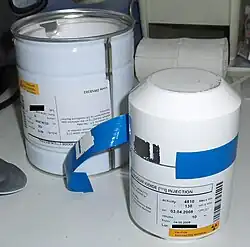

Das verwendete radioaktive Jod-Isotop Jod-131 steht als Natriumjodid in Kapselform und in wässriger Lösung zur Verfügung. Es wird in der Regel peroral verabreicht, kann in Ausnahmefällen (zum Beispiel bei ausgeprägten Schluckstörungen) auch intravenös appliziert werden. Bei peroraler Aufnahme wird das Jod rasch über die Magenschleimhaut aufgenommen und an das Blut abgegeben (Resorption). Über den Natrium-Jodid-Symporter gelangt das Jod in die Schilddrüsenzelle und wird letztlich im Schilddrüsenfollikel gespeichert. Unter der Wirkung von TSH oder TSH-Rezeptor-Autoantikörpern ist die Aufnahme von Jod in die Schilddrüsenzellen erhöht. Autonome Anteile der Schilddrüse nehmen Jod unabhängig vom TSH auf.